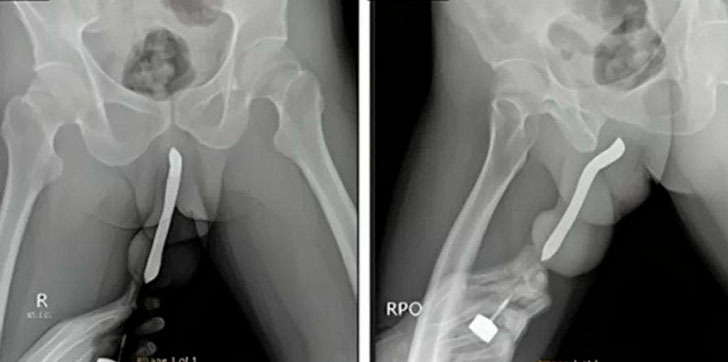

Al analizarlo, los médicos del Hospital Académico General Soetomo, en Java Oriental, determinaron que tenía una “deformidad tipo berenjena”, un signo claro de fractura de pene.

Los cirujanos sometieron al paciente a una intervención quirúrgica de dos horas, con el fin de retirar el cuerpo extraño y reparar su pene roto.

“El paciente sufrió una lesión en el pene durante la relación sexual en posición de mujer encima la noche anterior”, escribieron los facultativos en un artículo publicado en Journal of Surgery Case Reports.